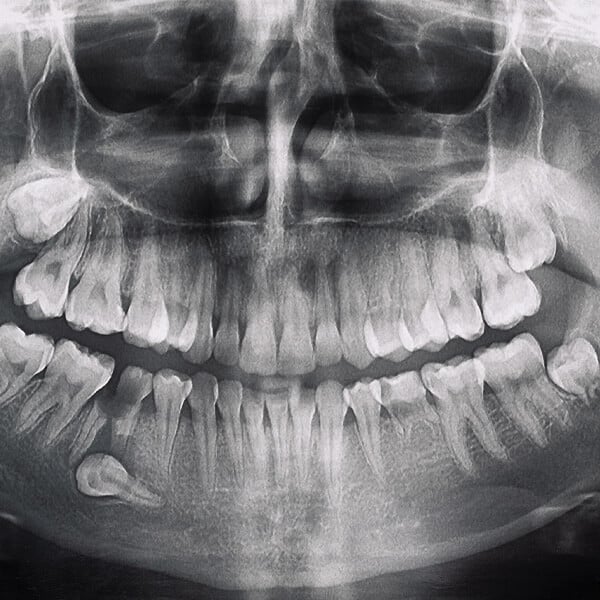

Pierwszym krokiem w leczeniu zatrzymanych zębów jest szczegółowa konsultacja stomatologiczna i diagnostyka. Wykonujemy panoramiczne zdjęcia rentgenowskie oraz stożkową tomografię komputerową, aby dokładnie ocenić położenie zatrzymanego zęba oraz jego wpływ na otaczające tkanki i struktury zębowe.

Zanim przystąpimy do zabiegu, pacjent przechodzi szczegółową konsultację stomatologiczną, która obejmuje badanie jamy ustnej oraz diagnostykę obrazową (pantomogram, tomografia komputerowa). Na tej podstawie opracowujemy indywidualny plan leczenia.

Pierwszym krokiem w przygotowaniu do leczenia protetycznego jest szczegółowa konsultacja stomatologiczna. Podczas tej wizyty przeprowadzamy wywiad medyczny, aby zrozumieć historię zdrowia pacjenta oraz jego oczekiwania i potrzeby. Następnie wykonujemy szereg badań diagnostycznych, w tym zdjęcia rentgenowskie (Pantomogram, RVG) oraz tomografię komputerową, aby dokładnie ocenić stan jamy ustnej, kości i tkanek miękkich.